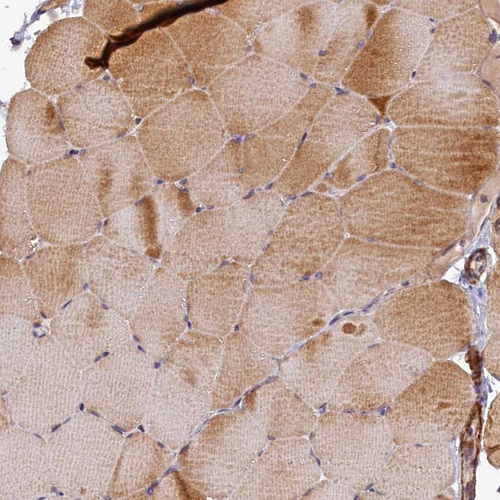

Immunohistochemical staining of human cerebral cortex shows moderate granular cytoplasmic positivity in neurons.